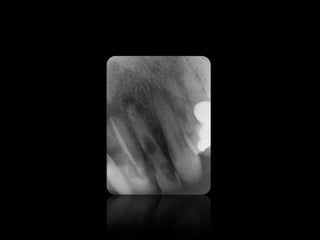

ABSCESO PERIAPICAL

14.